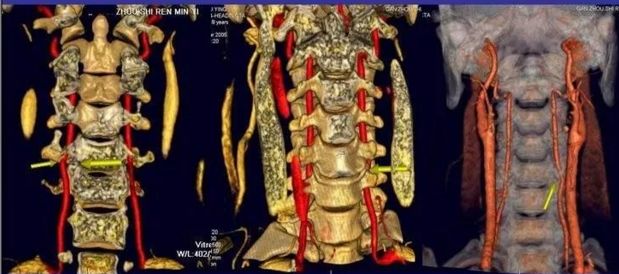

脊髓型颈椎病

髓型颈椎病的发病率占颈椎病的12-20%,也是目前许多骨科,和大夫非常头痛的一种颈椎病类型,因为他的影响十分严重。甚至可造成肢体瘫痪,脊髓型颈椎病致残率高。

脊髓型颈椎病通常起病缓慢,以40-60岁的中年人为多。脊髓型颈椎病的发病,和严重程度,往往和有无颈椎管狭窄有很大关系。

症状

1.多数患者首先出现一侧或双侧下肢麻木、沉重感,随后逐渐出现行走困难。上下楼梯时需要借力。严重者步态不稳、行走困难。患者双脚有踩棉感。

2.出现一侧或双侧上肢麻木、疼痛,双手无力、不灵活,像写字、系扣等精细动作难以完成。严重者甚至不能自己进食。

3.躯干部出现感觉异常,患者常感觉在胸腹部、或双下肢有如皮带样的捆绑感。同时下肢可有烧灼感、冰凉感。

4.部分患者出现排尿无力、尿频尿急、尿不尽、尿失禁或尿潴留等排尿障碍,大便密结等,性功能减退。